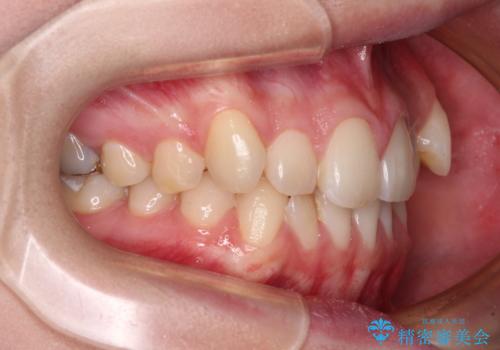

- 左右の八重歯を気にして来院された患者様です。

歯列としてはインビザラインでもワイヤー矯正でも対応できるものでしたが、インビザラインによる治療を希望されていました。

上顎の八重歯改善にインビザラインでは時間のかかってしまう可能性があり、更には口元が治療前よりも突出してしまう可能性があったため、補助装置により八重歯を事前に引き込んでおくことで、インビザラインによる治療をスムーズに行えるように計画しました。

補助装置を使用したことで、口元が突出することもなく、スムーズに仕上げることができました。